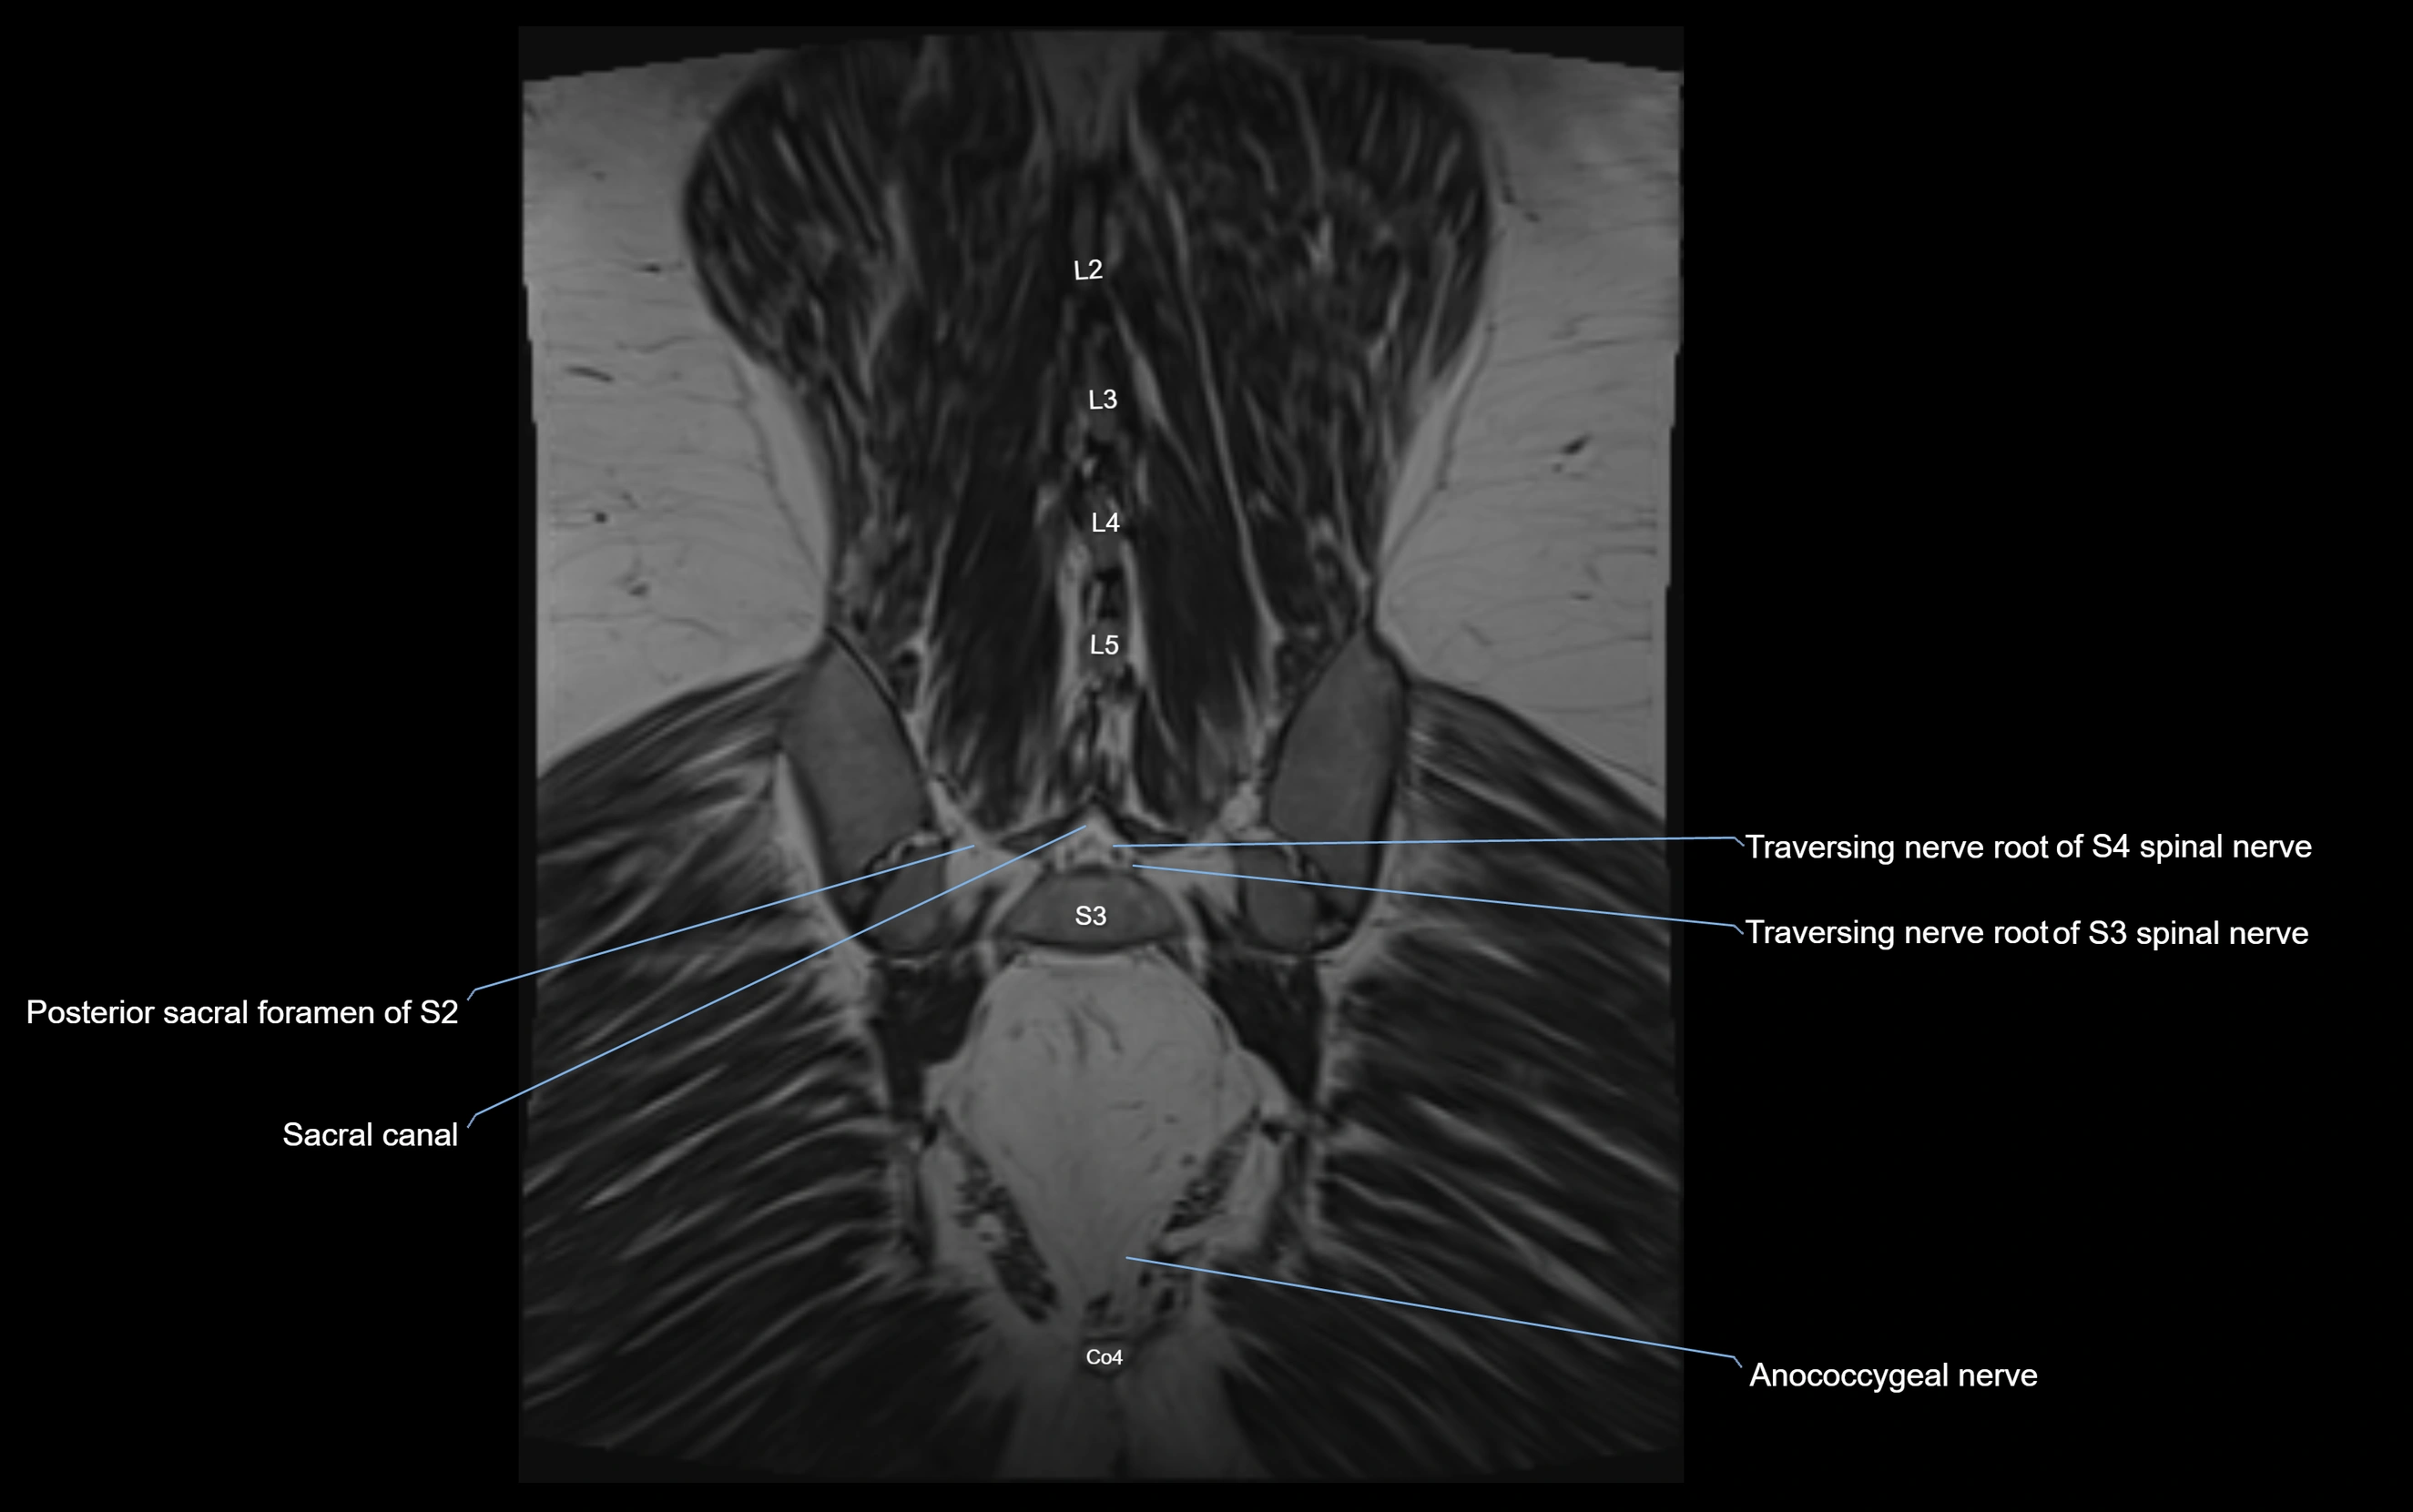

MRI image

image